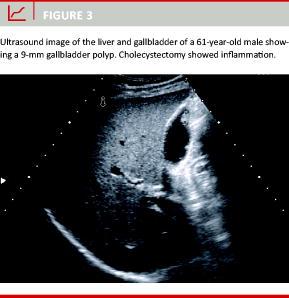

A total of 203 patients with GB polyps were included. The median age was 54 years (range of 19-95 years). There were 89 men (44%) and 114 women (56%). At baseline, 103 patients (50.7%) had one GB polyp, 29 patients (14.3%) had two GB polyps and 60 patients (29.5%) had five or more GB polyps. Simultaneously, coexisting gallstones were detected in ten patients (5%). The mean polyp size at baseline was 5 mm, with a standard deviation ± 3.9 and a range of 2-40 mm (Figure 2). In 175 patients (86%), GB polyp diameter was ≤ 6 mm, and in 143 patients (70%) the GB polyp was ≤ 5 mm. In nine patients, the GB polyp size at baseline was 10 mm or larger (Figure 3).